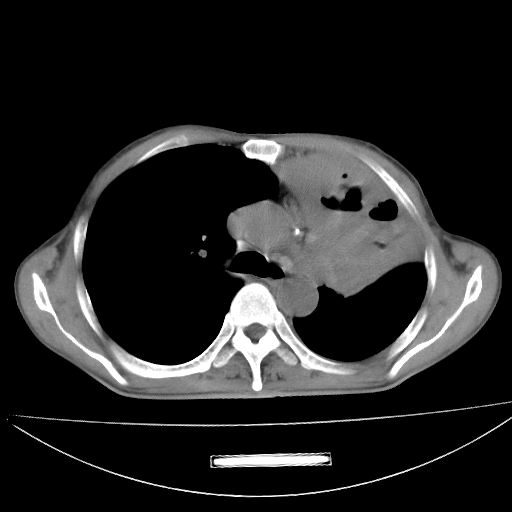

以下是引用杀毒软件在2009-4-28 17:58:00的发言:[br]考虑----左肺慢性肺脓肿形成继发上叶含气不良---抗炎后复查---待排肿瘤所致[br][br][本贴已被 杀毒软件 于 2009-4-28 18:01:26 修改过]